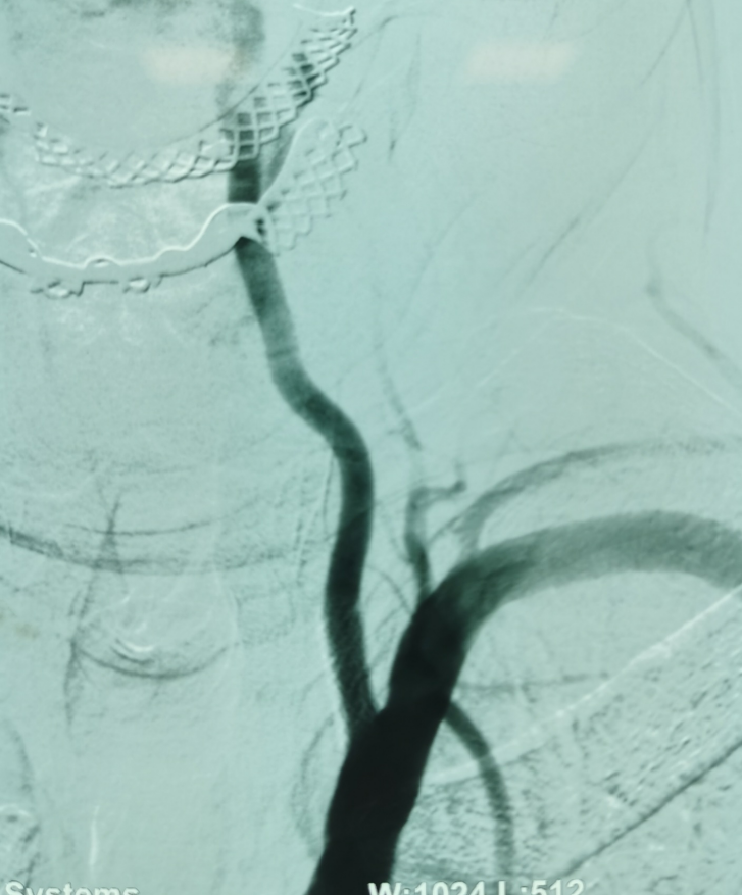

颈动脉支架

植入血管成形术

椎动脉支架